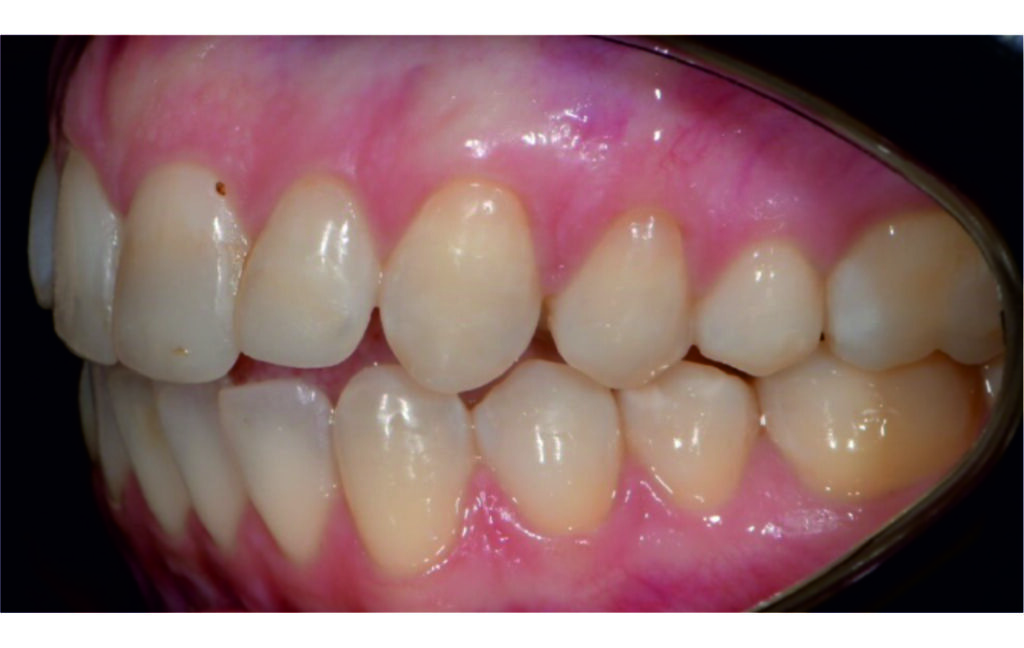

Initial Photos and datas

Angle Class II 2mm on the right, Angle Class II 2mm on the left, light mandibular asymmetry to the right, lower central line 1mm to the right, upper central line 1,5mm to the left, 1mm overjet and overbite. Sagittal asymmetry of upper dental arch. Light crowding upper and lower frontal segments, severe attrition of posterior teeth, night bruxism. Normal sagittal position of both jaws, high angle case, steep mandibular ramus,excessive lower facial height, open bite tendency.

The case initially presented as a moderate Class II on the right and a Class II tendency on the left, with tapered dental arches and an anterior open bite extending to tooth 26 in segment II.

In segment I, the open bite reached up to the first premolar.

A 1.5 mm deviation of the upper dental midline to the patient’s left was noted, along with a slight mandibular midline shift to the right, likely due to asymmetrical mandibular growth observed in the facial structure. Severe mesial rotations of teeth 16 and 26 were evident in the initial records. As derotation of 16, 26, 17, and 27 progressed up to aligner 16, the premolars in segments I and II moved distally, resulting in a bilateral Class I relationship, as intended in the initial treatment plan.